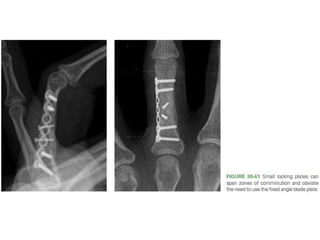

• #90 Figure 30-61 Small locking plates can span zones of comminution and obviate the need to use the fixed angle blade plate.